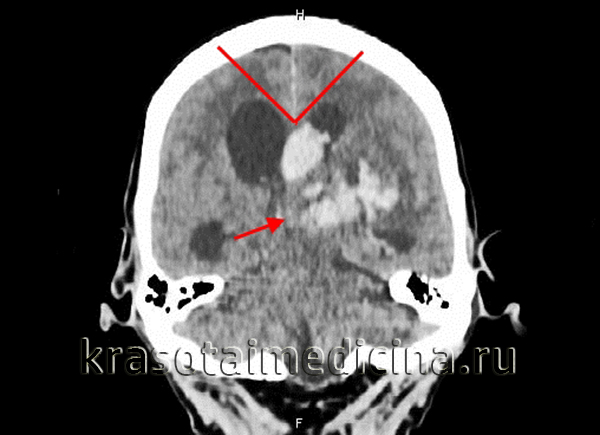

КТ головного мозга. Окклюзионная гидроцефалия, обусловленная массивной внутримозговой гематомой. Стрелка – поджатый 3-й желудочек

- Внутримозговая гематома. Формируется вследствие черепно-мозговой травмы (в том числе внутричерепной родовой травмы), геморрагического инсульта. Окклюзионная гидроцефалия обусловлена сдавлением путей оттока ликвора образовавшейся гематомой.

Закупорка, сдавление ликвороносных трактов приводит к нарушению оттока и накоплению цереброспинальной жидкости в желудочках мозга. Объем желудочков увеличивается, в условиях замкнутого внутричерепного пространства это влечёт повышение давления внутри черепной коробки. Скорость нарастания интракраниальной гипертензии зависит от степени и механизма окклюзии. Обтурация отверстия Монро ведёт к увеличению бокового желудочка, закупорка на уровне сильвиевого водопровода — к расширению III и обоих боковых желудочков, на уровне отверстий Можанди и Люшка — к тотальной дилатации желудочковой системы.

Окклюзионная гидроцефалия опухолевого генеза формируется постепенно, при посттравматической гематоме — в течение нескольких дней. Окклюзия кровяным сгустком, частью внутрижелудочковой опухоли происходит внезапно, приводит к острой гидроцефалии. Интравентрикулярные новообразования, коллоидные кисты способны вызывать окклюзионные кризы — преходящую блокировку ликвороциркуляции, возникающую при смещении образования. Значительная внутричерепная гипертензия обуславливает сдавление мозговых тканей, питающих сосудов. Возникает гипоксия, дисметаболические изменения, ведущие к гибели нейронов. Продолжающийся рост давления вызывает смещение церебральных структур (масс-эффект), приводящее к тяжёлым осложнениям.